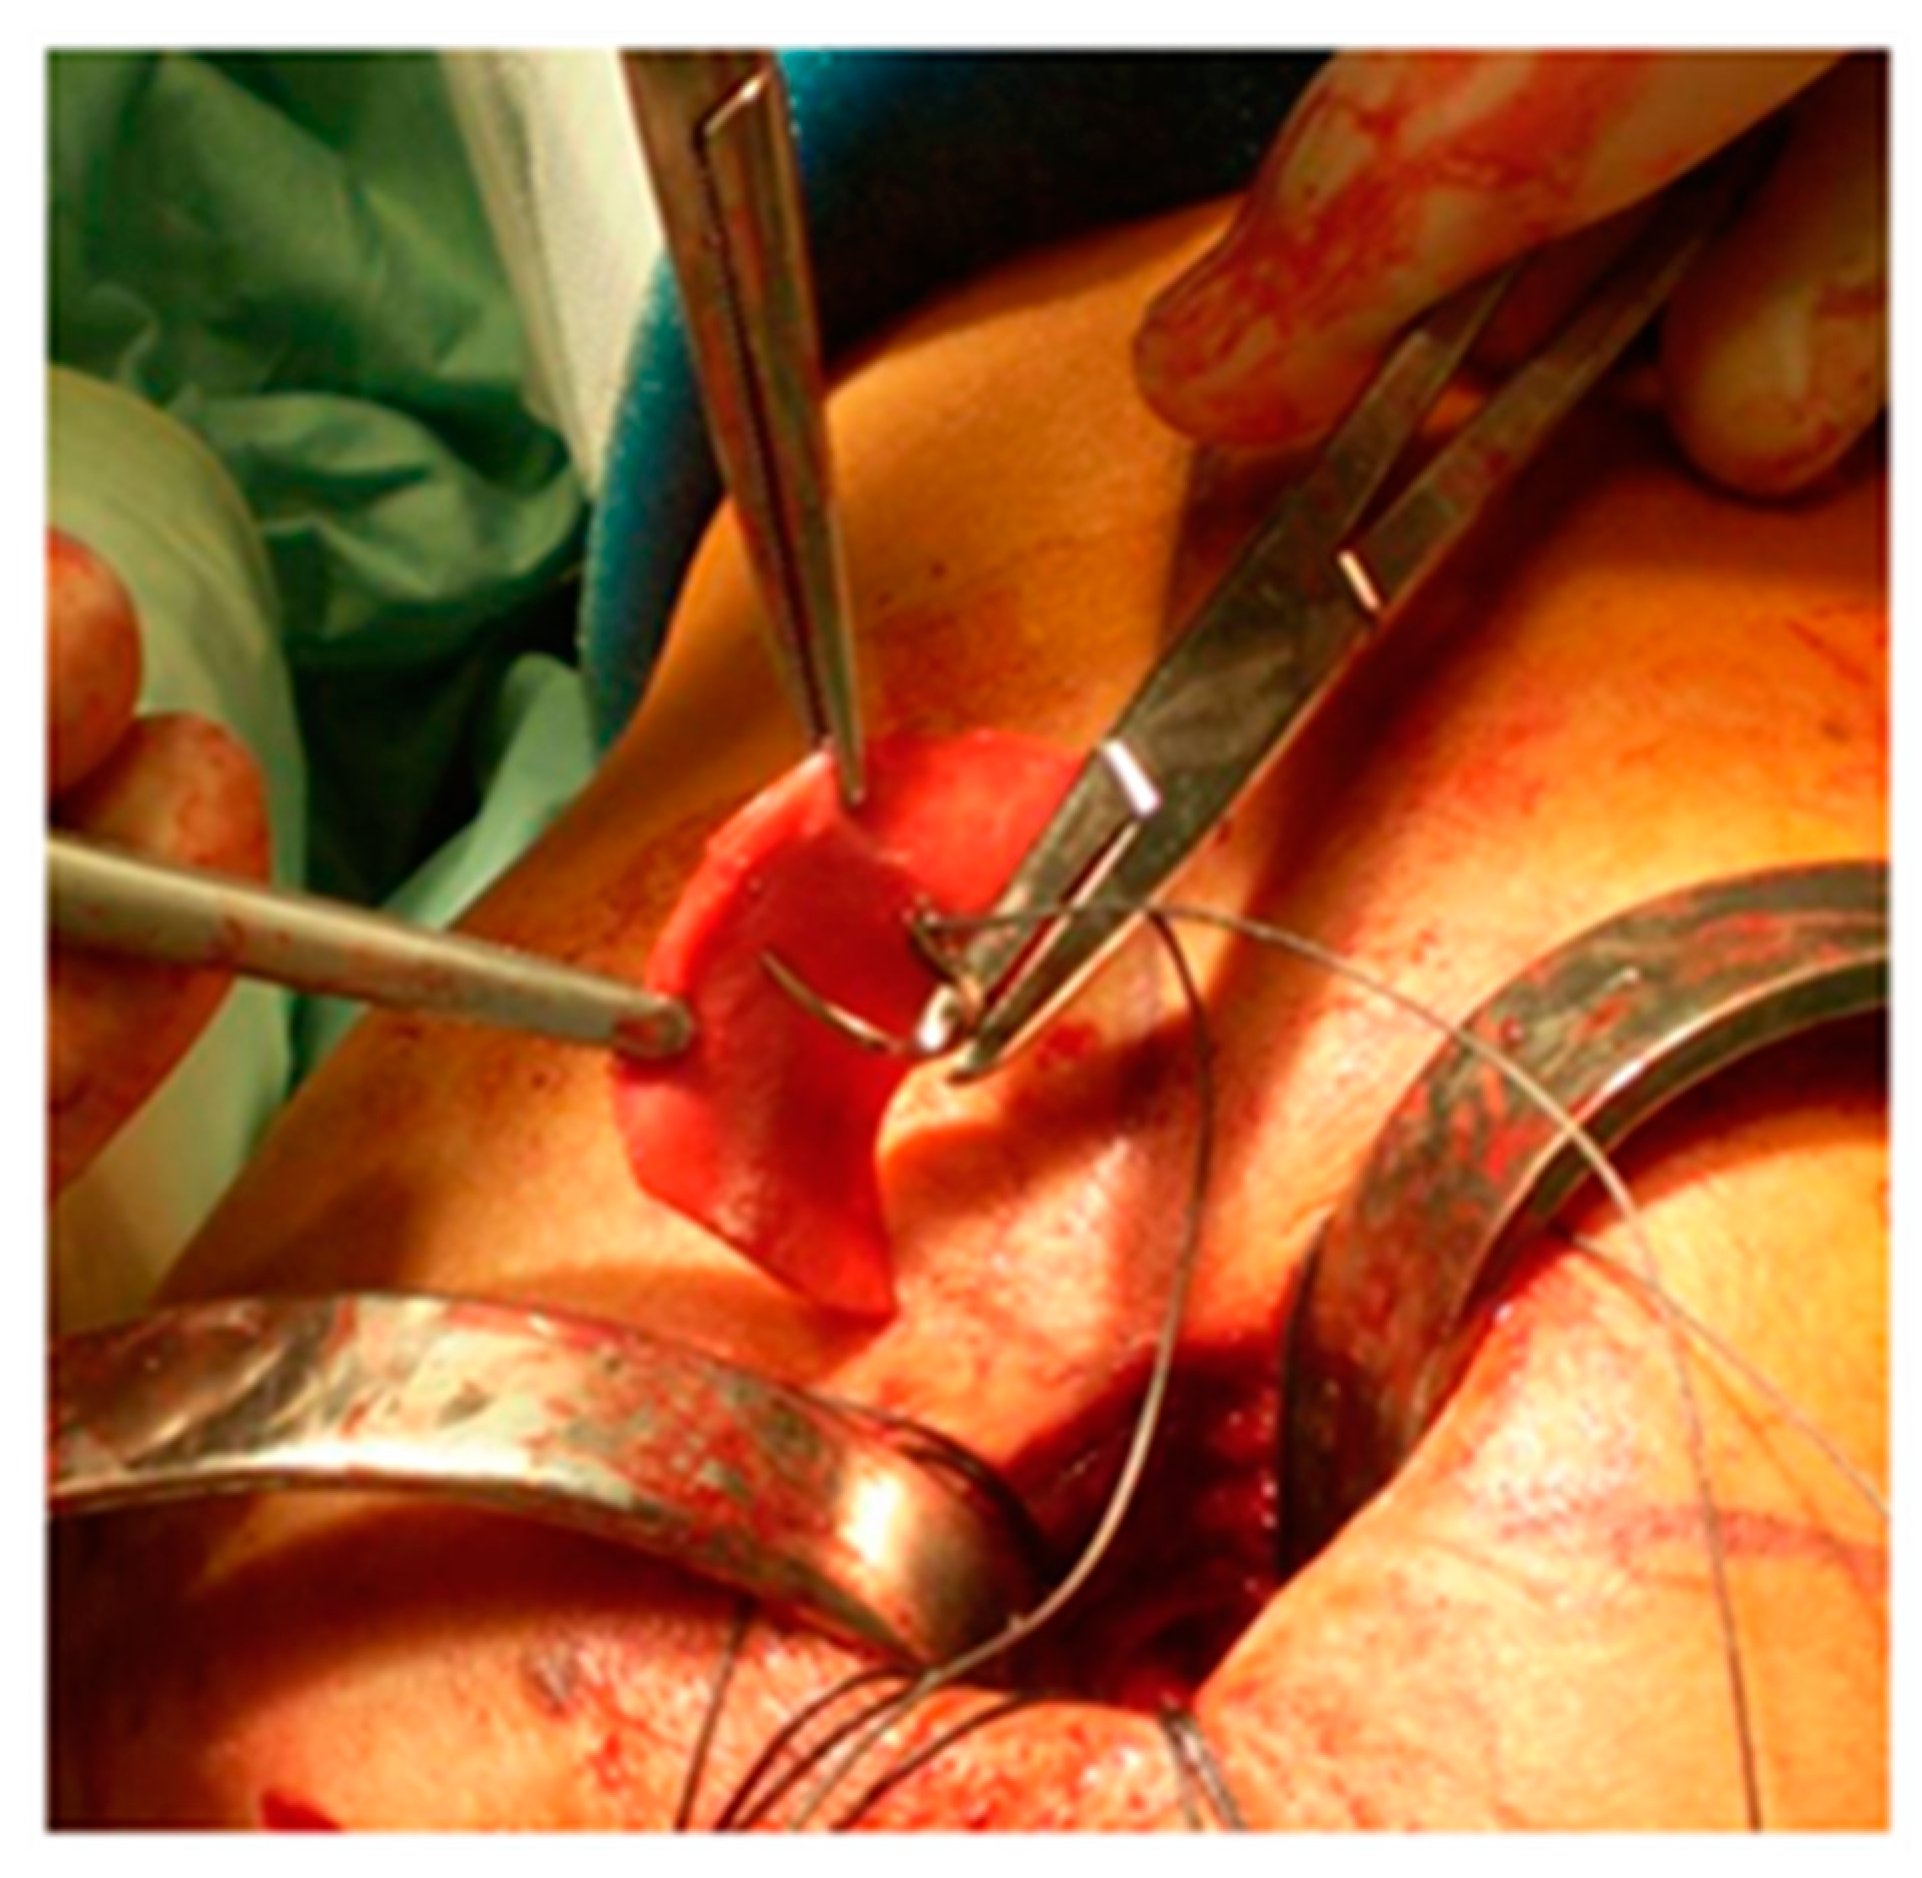

The edges of the RC tear were identified and debrided; tendon mobilization was attempted to verify if a primary tendon-to-bone repair was possible. When re-insertion to the footprint was possible, but the tendon tissue quality was clinically considered poor, a patch was sutured with non-absorbable stitches on the bursal side of the RC and reinserted together with the tendon onto the respective tuberosity over the anchors (Figure 1). The RC tendon was retracted and non-mobilizable, confirming the impossibility of a direct tendon-to-bone repair sutured to the edges of the tendon stump with non-absorbable sutures and then reinserted into the tuberosity with anchors (Figure 2). In both techniques (augmentation and bridging), and with both the biological implant (xenograft of collagen of porcine origin and DED-LYO allograft), the patch was cut to the appropriate size corresponding to the gap to be reinforced or covered. To control bleeding, in the absence of contraindications, tranexamic acid was administered both intravenously and locally, as previously described [17].

Figure 1. DED-LYO patch augmentation procedure.